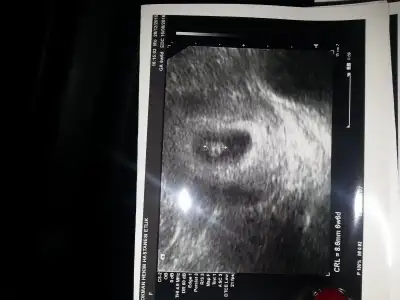

Kizlar benim bebisimi de yorumlar misiniz

kıza benziyor :) kesenin sağındaysa kız oluyor genelde. Rabbim gönlüne göre versin.

O zaman benim kizmi cnm bakarmisin bana ekliyorum.. Karindan yarin ceker sanirim 6 hafta 5 gunluk

bu vajinalse erkek oluyo :)

Hadi ya ama solda degilmi bebek nasil bakiliyor.. Yani soldaysa sagda olmus olmuyormu... Bi ben anlamadim sunu :)

bak benim açtığım bi konu var. buna ramzi teorisi deniliyor bi incele istersen uzun uzun yazdım.